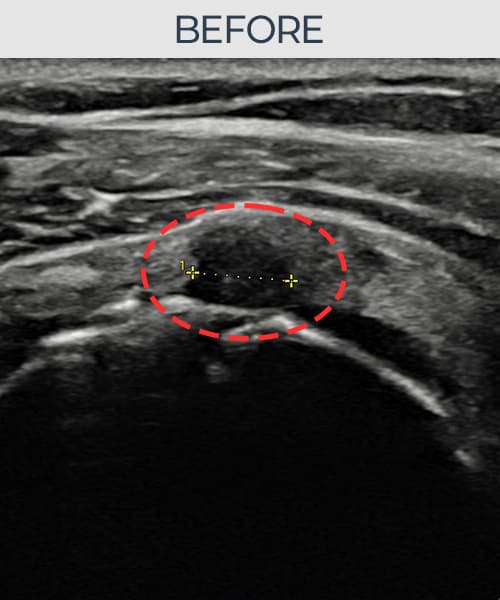

시술 전 초음파 측정 결과 파열 크기는 6mm × 3mm (힘줄 두께의 약 35% 결손)로 확인되었습니다. 시술 전 초음파에서 운동 부상으로 인한 회전근개 결손과 힘줄 내 불균질 에코 소견이 확인되었습니다. 시술 후 초음파에서 결손 부위에 섬유성 재생 조직이 형성되었으며, 힘줄 두께와 연속성이 정상 수준으로 회복된 것이 관찰되었습니다.

30대 후반 남성 환자분으로, 주 5회 웨이트 트레이닝을 즐기시는 분이었으며 운동 중 무리한 덤벨 프레스 동작에서 어깨를 다치셨습니다. 부상 후에도 운동을 지속하다 통증이 심해져 내원하셨고, 초음파 검사에서 회전근개 부분파열이 확인되었습니다. 젊은 연령대임에도 파열이 이미 진행된 상태였으며, 장기적인 운동 복귀를 위해 구조적 봉합이 필요하다고 판단하여 축소봉합술을 시행하였습니다. 시술 후 8주간 과도한 팔 사용을 제한하였고, 이후 단계적으로 재활 운동을 병행하였습니다. 4개월 후 가벼운 운동부터 재개하였으며, 최종 경과 관찰에서 힘줄 결손 부위의 완전한 재생이 확인되어 운동에 완전히 복귀하셨습니다.